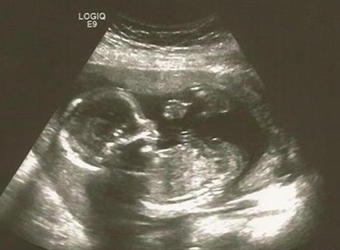

NT检查是一种孕期的筛查,主要是为了判断婴儿是否有畸形概率,而NT检查的图也属于超声影像的一种,那么NT图弯着就是男孩吗,女宝宝的NT图是平躺着的吗?更多关…

NT检查是一项孕检,主要是为了筛查唐氏综合征的儿童,也是一种超声检查,据说NT图男女宝宝是可以看出区别的,那么NT男女宝宝区分图片是什么,三个月的NT可以看…

在国外还是有通过超声胎儿性别的方法的,其中最简单的方式就是看宝宝的第二性征,那么NT检查图看男女看哪个角度呢,NT胎儿男女区别对照图,更多关于生男生女的…